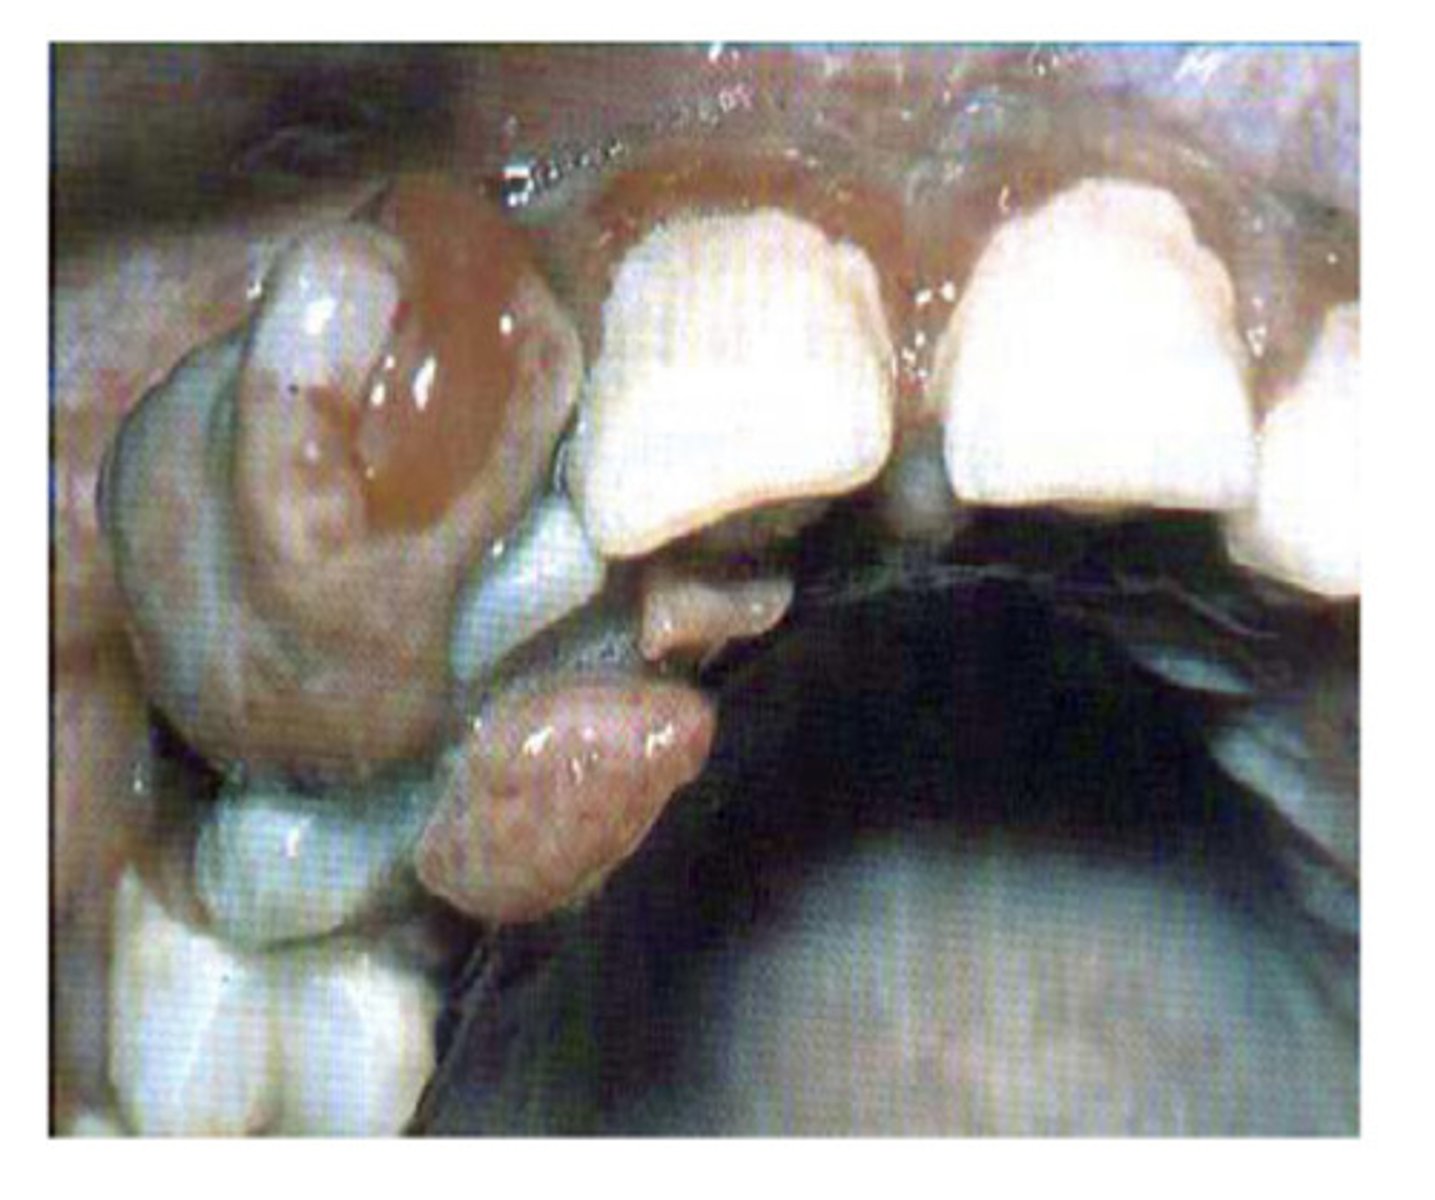

What is this?

Peripheral giant cell granuloma (epulis)

Unknown aetiology, red, haemorrhagic and soft, occasional superficial bone erosion - usually excised - what am i?